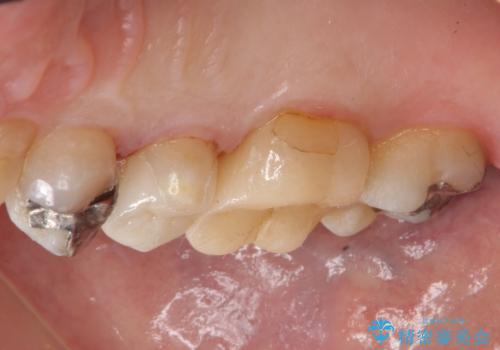

- 銀歯の下が虫歯になっていたため、虫歯を取り、セラミックインレーで修復しました。

- emaxプレスインレー 7万円費用は治療当時の料金となります

銀歯が合っていないなどは、見た目だけではわかりにくいことがあります。

早めに見つけて、症状が出る前に治すことが大事です。